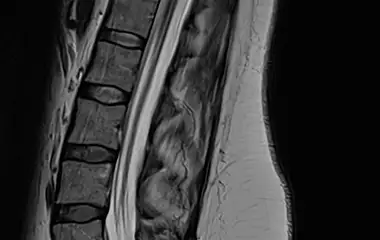

Der Bereich Hydrozephalus, Chiari-Malformation und Tethered-Cord-Syndrom umfasst die Diagnostik und Behandlung komplexer Erkrankungen des Liquorsystems sowie des Gehirns und Rückenmarks. Wir behandeln angeborene und erworbene Formen des Hydrozephalus, einschließlich des Normaldruckhydrozephalus, der sich häufig durch Gangstörungen, kognitive Veränderungen und Blasenfunktionsstörungen äußert. Ein weiterer Schwerpunkt ist die Chiari-Malformation, bei der es zu einer Verlagerung von Kleinhirnanteilen in den Spinalkanal kommen kann und die vielfältige neurologische Symptome verursachen kann. Das Tethered-Cord-Syndrom beschreibt eine krankhafte Fixierung des Rückenmarks, die sowohl in klassischer als auch in okkulter Form auftreten und zu Schmerzen, neurologischen Defiziten oder Funktionsstörungen führen kann. Ziel unserer Behandlung ist es, neuralen Strukturen zu entlasten, eine weitere Schädigung zu verhindern und die Lebensqualität der Patientinnen und Patienten zu verbessern. Grundlage hierfür sind eine präzise Diagnostik, individuell abgestimmte Therapiekonzepte und eine umfassende, verständliche Aufklärung.

Bei Hydrozephalus bieten wir verschiedene Formen der Liquorableitung an, darunter den Liquorshunt und den ventrikuloperitonealen Shunt (VP-Shunt), individuell angepasst an die jeweilige Erkrankung. Als alternative, shuntunabhängige Therapie führen wir die endoskopische Drittventrikulozisternostomie (ETV) durch, sofern die anatomischen Voraussetzungen gegeben sind. Patientinnen und Patienten mit Arnold-Chiari-Malformation behandeln wir durch eine gezielte mikrochirurgische Dekompression, um den Liquorfluss zu verbessern und neurologische Symptome zu lindern. Beim Tethered-Cord-Syndrom, einschließlich okkulter Formen, setzen wir auf ein minimalinvasives Detethering zur schonenden Entlastung des Rückenmarks.